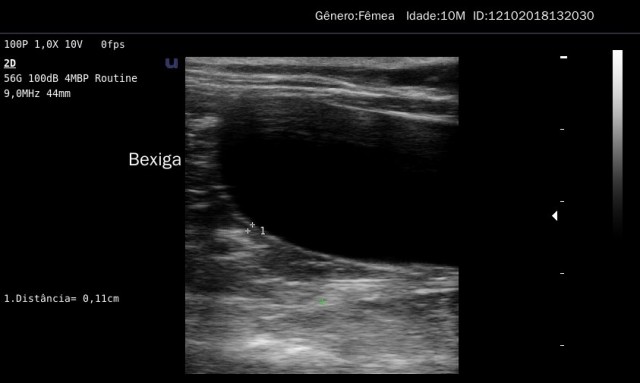

Exame de Ultrassonografia

A ultrassonografia é um exame que interpreta o eco produzido pelos sons para gerar imagens computado...

Saiba mais